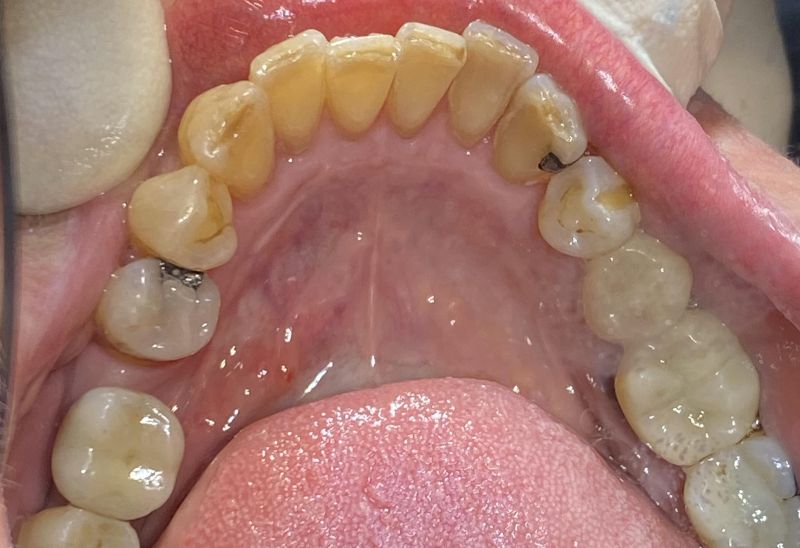

Prima e dopo l'apparecchio invisibile

In questa sezione mostreremo risultati reali ottenuti con l’ortodonzia invisibile a Roma. I cambiamenti riguardano non solo i denti, ma anche l’armonia del viso, la postura orale e l’autostima.